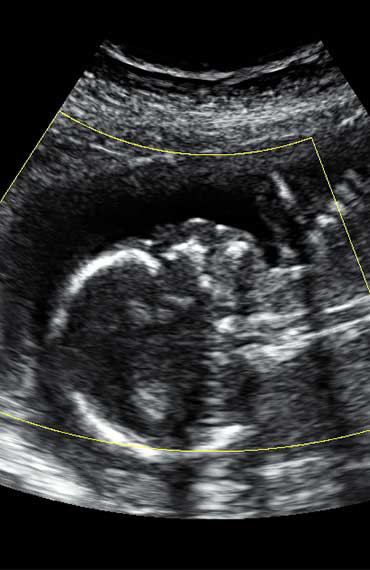

All photos are from our equipment and are of our actual clients.